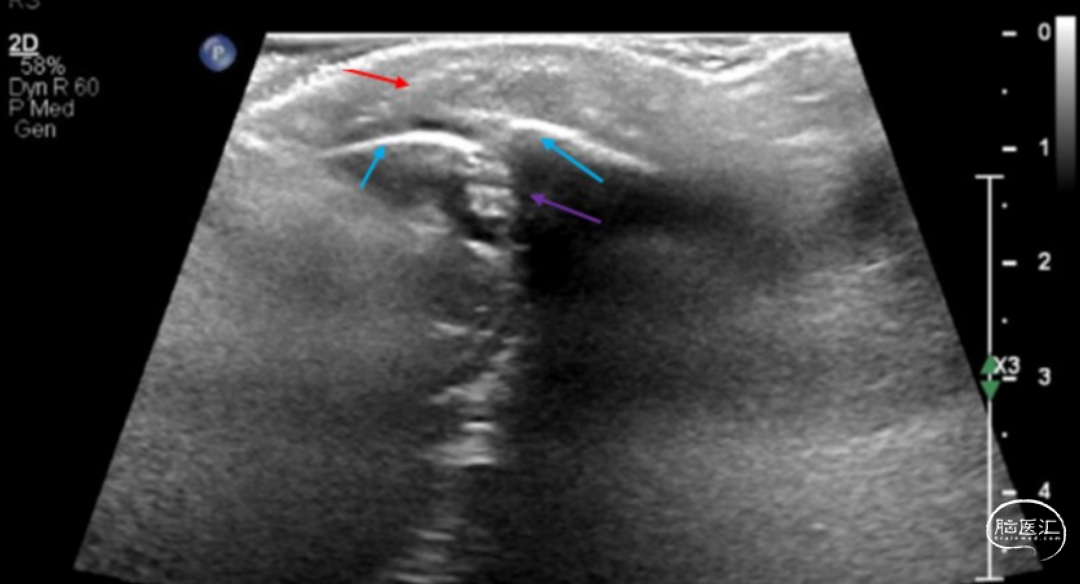

● 患儿为10个月大男婴,患有Lennox-Gastaut综合征和发育倒退,常规神经科门诊检查时偶然发现枕部皮样囊肿。患儿母亲称其枕部自出生起就有肿块,且大小间歇性变化。检查发现枕部中线处有一柔软、可压缩、可移动的肿块,存在可触及的茎,提示可能有颅内延伸,但未完全附着于颅骨。超声显示肿块呈纺锤形,回声增强,延伸至枕骨板障空间,颅骨缺损较小,未见脑组织(图1)。

图1. 超声显示可能的皮样囊肿(红色箭头),向下延伸(紫色箭头)至枕骨(蓝色箭头)。